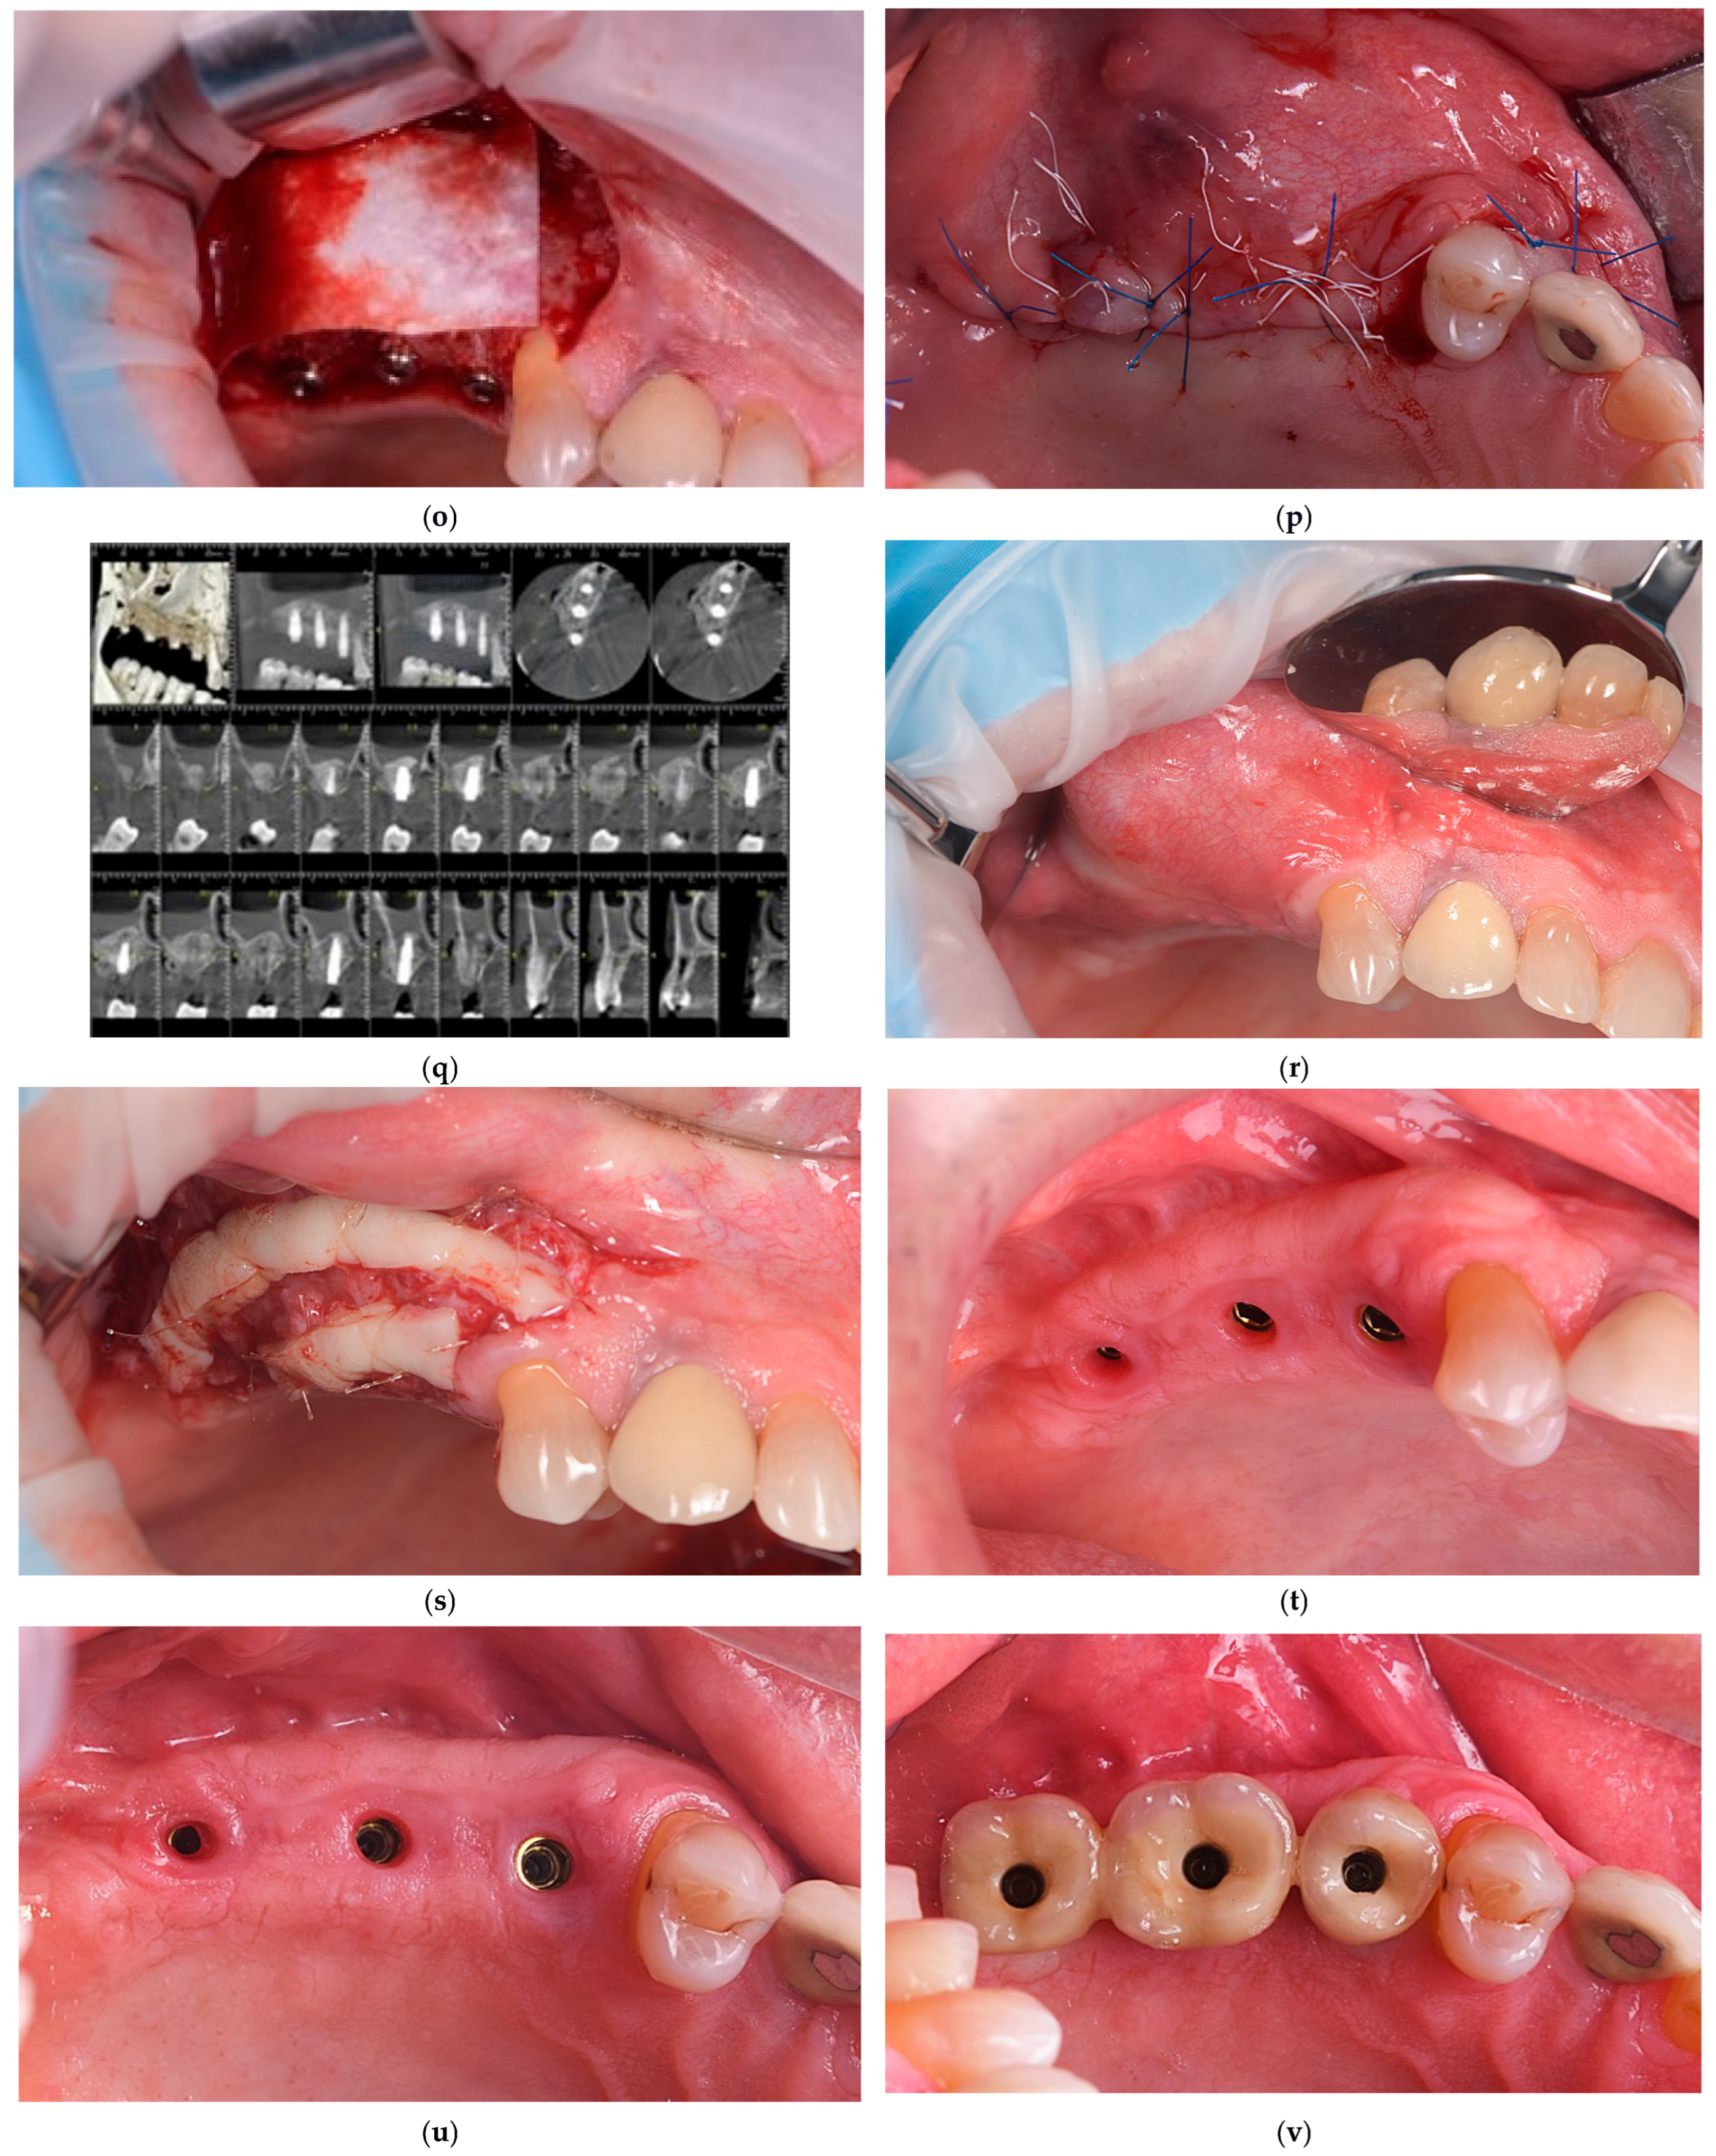

| Day 0 | Lateral sinus augmentation | Collagenated porcine xenograft (THE Graft™); lateral window approach; one case: controlled Schneiderian membrane perforation for mucocele removal and collagen membrane repair |

| Weeks 1–2 | Initial healing | No postoperative complications; uneventful soft tissue healing |

| Months 3–8 | Implant placement and biopsy | Core specimens collected during implant osteotomy; histology (H&E, Masson–Goldner) + TRAP staining |

| 3–4 months after implant placement | Prosthetic loading | Final implant-supported restorations delivered; functional loading commenced |

| Months 12–52 | Follow-up period | Stable marginal bone levels (<1 mm first year); no complications; graft volume maintained |

| 46.8 months (mean) | Long-term evaluation | All implants functional; radiographic and clinical stability confirmed |

| 52.2 months (max) | Long-term | CBCT and periapical radiographs from available case demonstrating stable bone height and osseointegration |